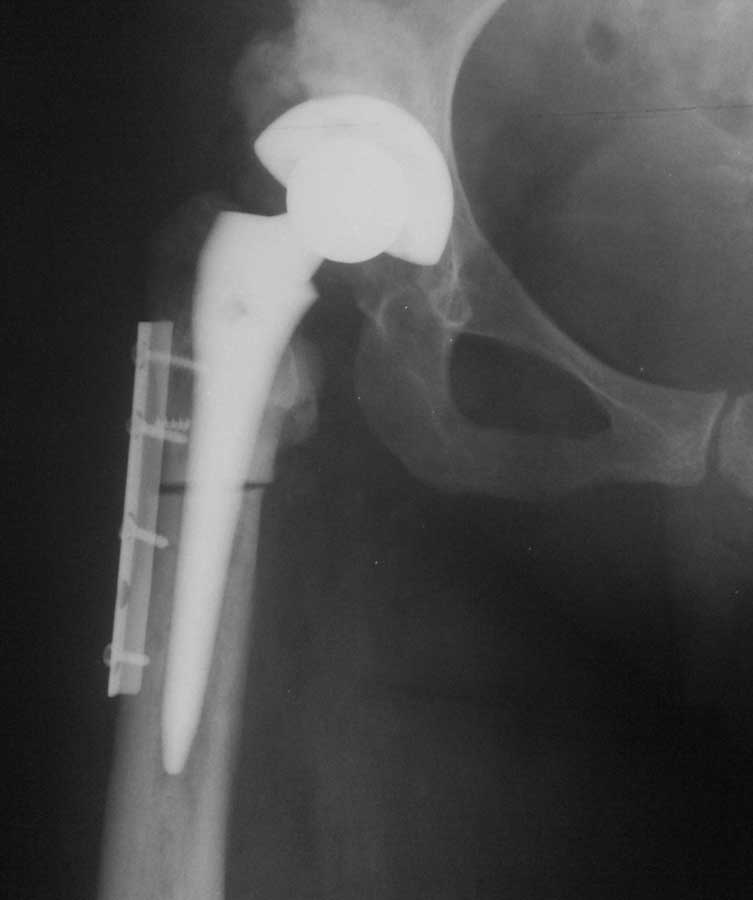

Уважаемые коллеги, к нам поступила женщина 45 лет с такой вот ситуацией:

Операция около 1,5 месяцев назад: тотальное б/ц эндопротезирование с остеотомией проксимального отдела бедра. Послеоперационный период - без особенностей, рана зажила первично, выписана домой. В анамнезе в детском и юношеском возрасте несколько оперативных вмешательств на вертлужной впадине и бедре по поводу врожденного вывиха бедра, судя по рубцам, протекавшие не совсем гладко.